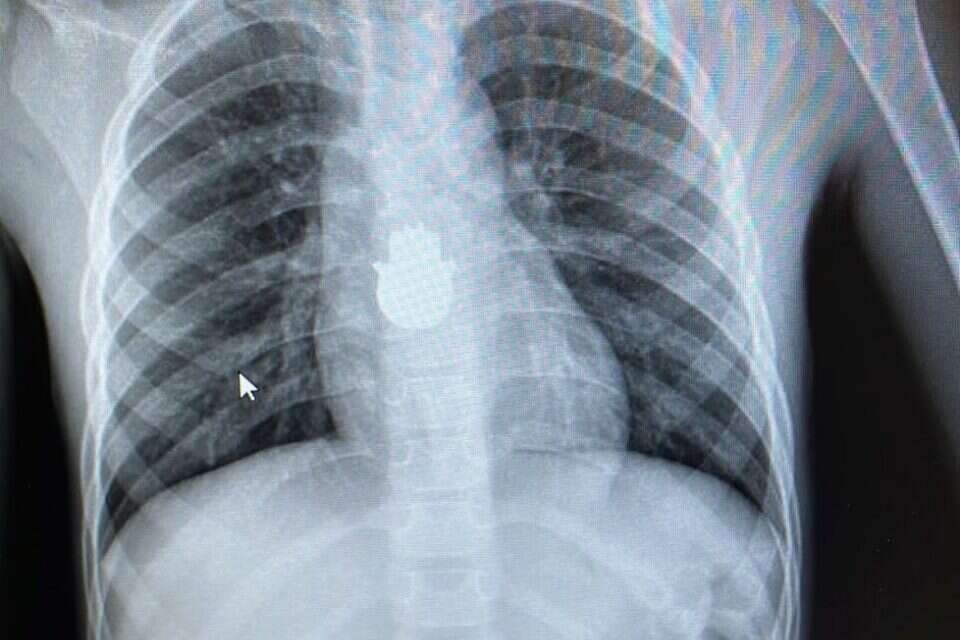

העצם הזר בצילום החזה. צילום: דוברות איכילוב

ילד בן שש הובל לחדר מיון ילדים "דנה" עקב כאבים בחזה. הוא לא סיפר כי בלע משהו וד"ר רינת נאור, מתמחה במיון, החליטה לשלוח לצילום חזה כחלק מהבירור. במהלך הבירור, נצפתה חמסה בגודל של 2.5 ס"מ על 1.5 ס"מ.